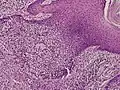

Microscopic histopathological examinations of the tumor tissues of all poroma variants stained with hematoxylin and eosin dyes reveal: a) basophilic "poroid cells" (i.e. small, cuboid-shaped cells with oval nuclei which resemble cells in the peripheral layer of the distal portion of eccrine sweat gland ducts[20]) that may form cords and broad columns extending downward from the epidermis; b) larger cuticular cells (i.e. squamous epithelial-like eosinophilic cells that resemble the luminal cells lining eccrine sweat gland ducts[20]); and in some cases c) clear cells (i.e. cells with small nuclei surrounded by pale cytoplasm).[3] Poroma tumor tissues may appear highly vascularized and/or have areas of necrosis, i.e. dead or dying cells. Hidroacanthoma simplex variants are mainly composed of poroid cells, few cuticular cells, and no clear cells and are confined to the epidermis; dermal ductal variants are mostly confined to the superficial dermis and are composed of small solid and cystic nodular aggregates of poroid, cuticular, and clear cells; poroid hidradenoma variants have large aggregates of solid and cystic components and extend deeper into the dermis or even subcutis; and eccrine poroma variants are composed of all three cell types but are primarily located in the epidermis and superficial dermis. Poromas may have 2 or more of these variants in the same tumor tissue and the variants typically have histopathology findings that are not clearly distinguishable from each other.[3]

Eccrine poroma